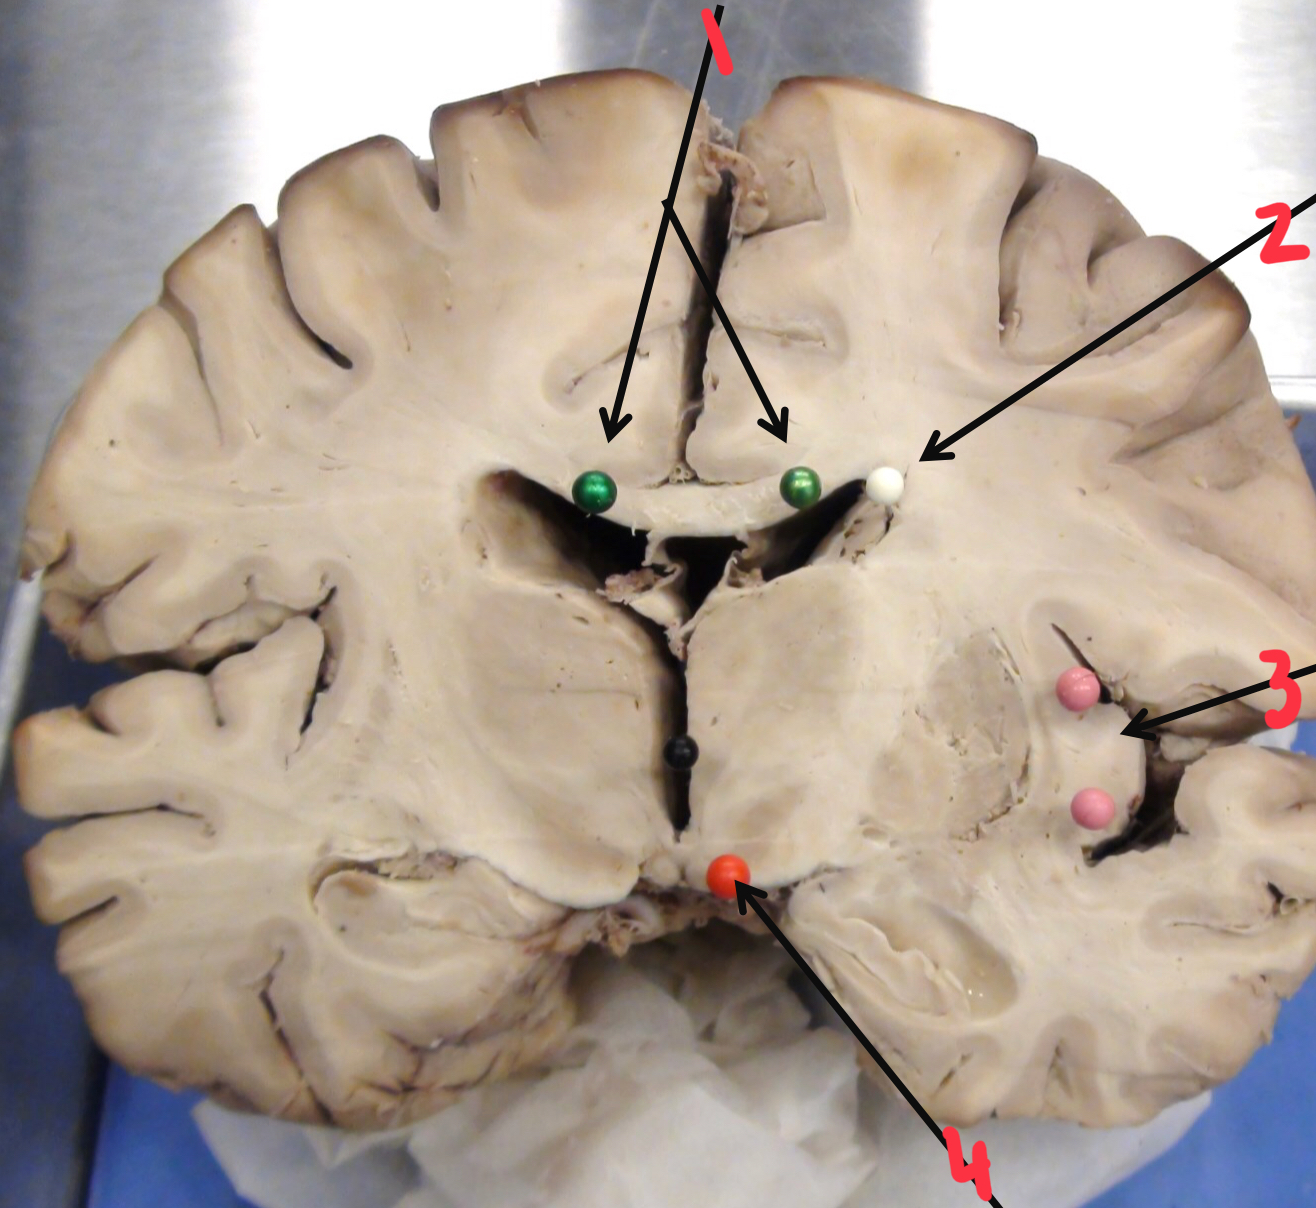

1

corpus callosum

2

caudate nucleus

3

insula (island of Reil)

4

mamillary body